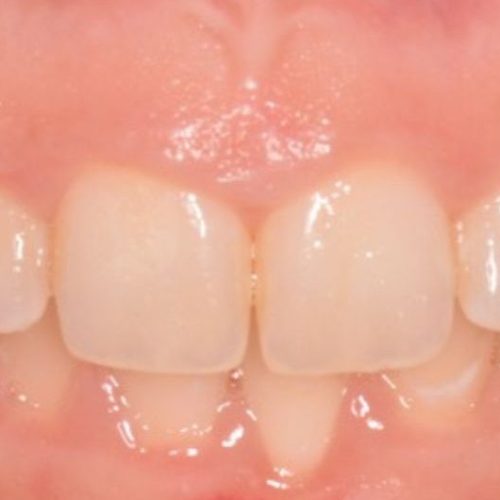

Cirugía periodontal y periimplantaria

Son aquellos actos dedicados a mejorar el pronóstico y facilitar la limpieza y mantenimiento de las piezas que se tratan. Cuando las circunstancias lo permiten existen técnicas y biomateriales para restaurar los tejidos perdidos. Estas maniobras sirven para tratar tanto dientes como implantes.